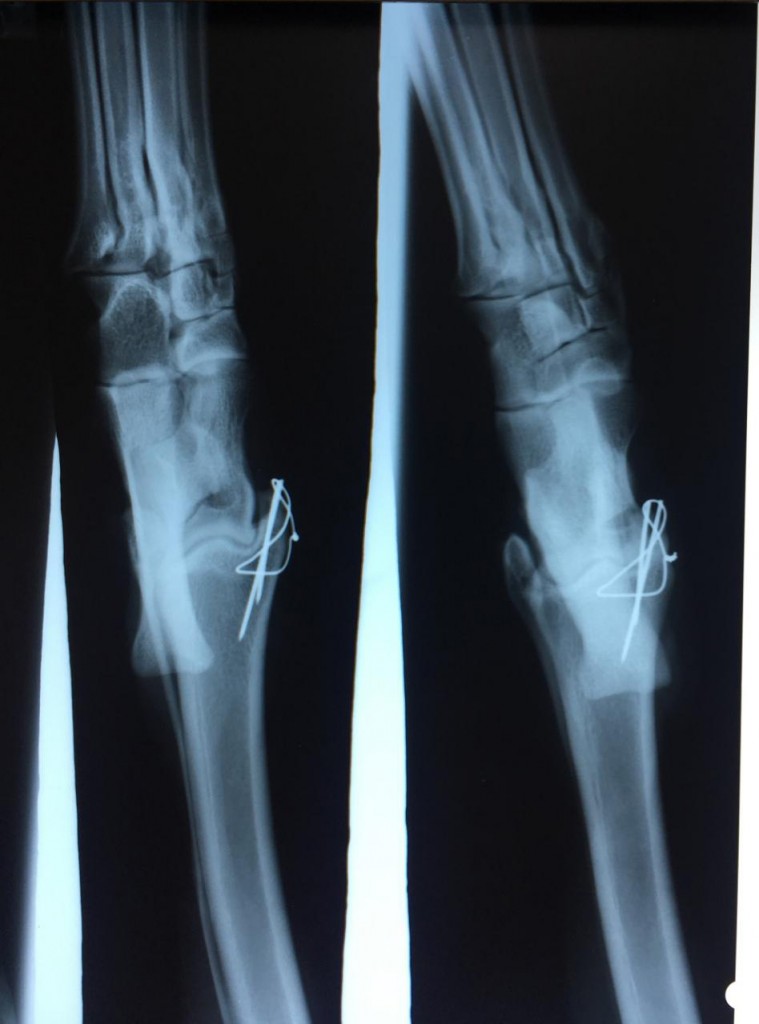

“He broke his leg in a really bad fall at Sandown in May and I didn’t think he would race again. He had two screws and zigzag wire put in to hold it together and I lasered him every morning and night for five months.

Burnout's x-ray

Burnout’s x-ray